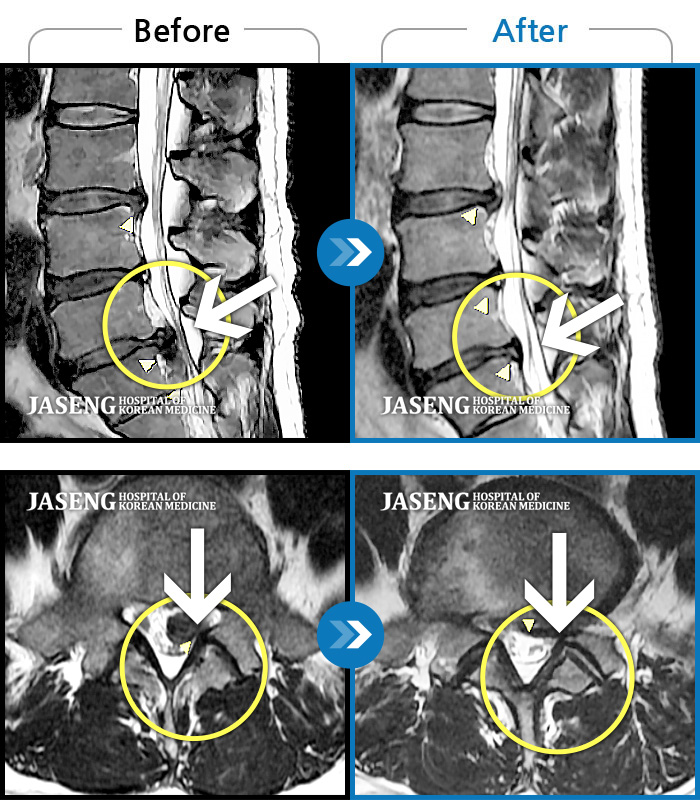

저는 협착증으로 병원에 입원해서 원장님께 치료 받고 있는 환자에요~

입원 전에는 다리가 저리고 땡겼는데 지금은 저림 증상은 거의 사라졌답니다

다 원장님 덕분이에요~~^^